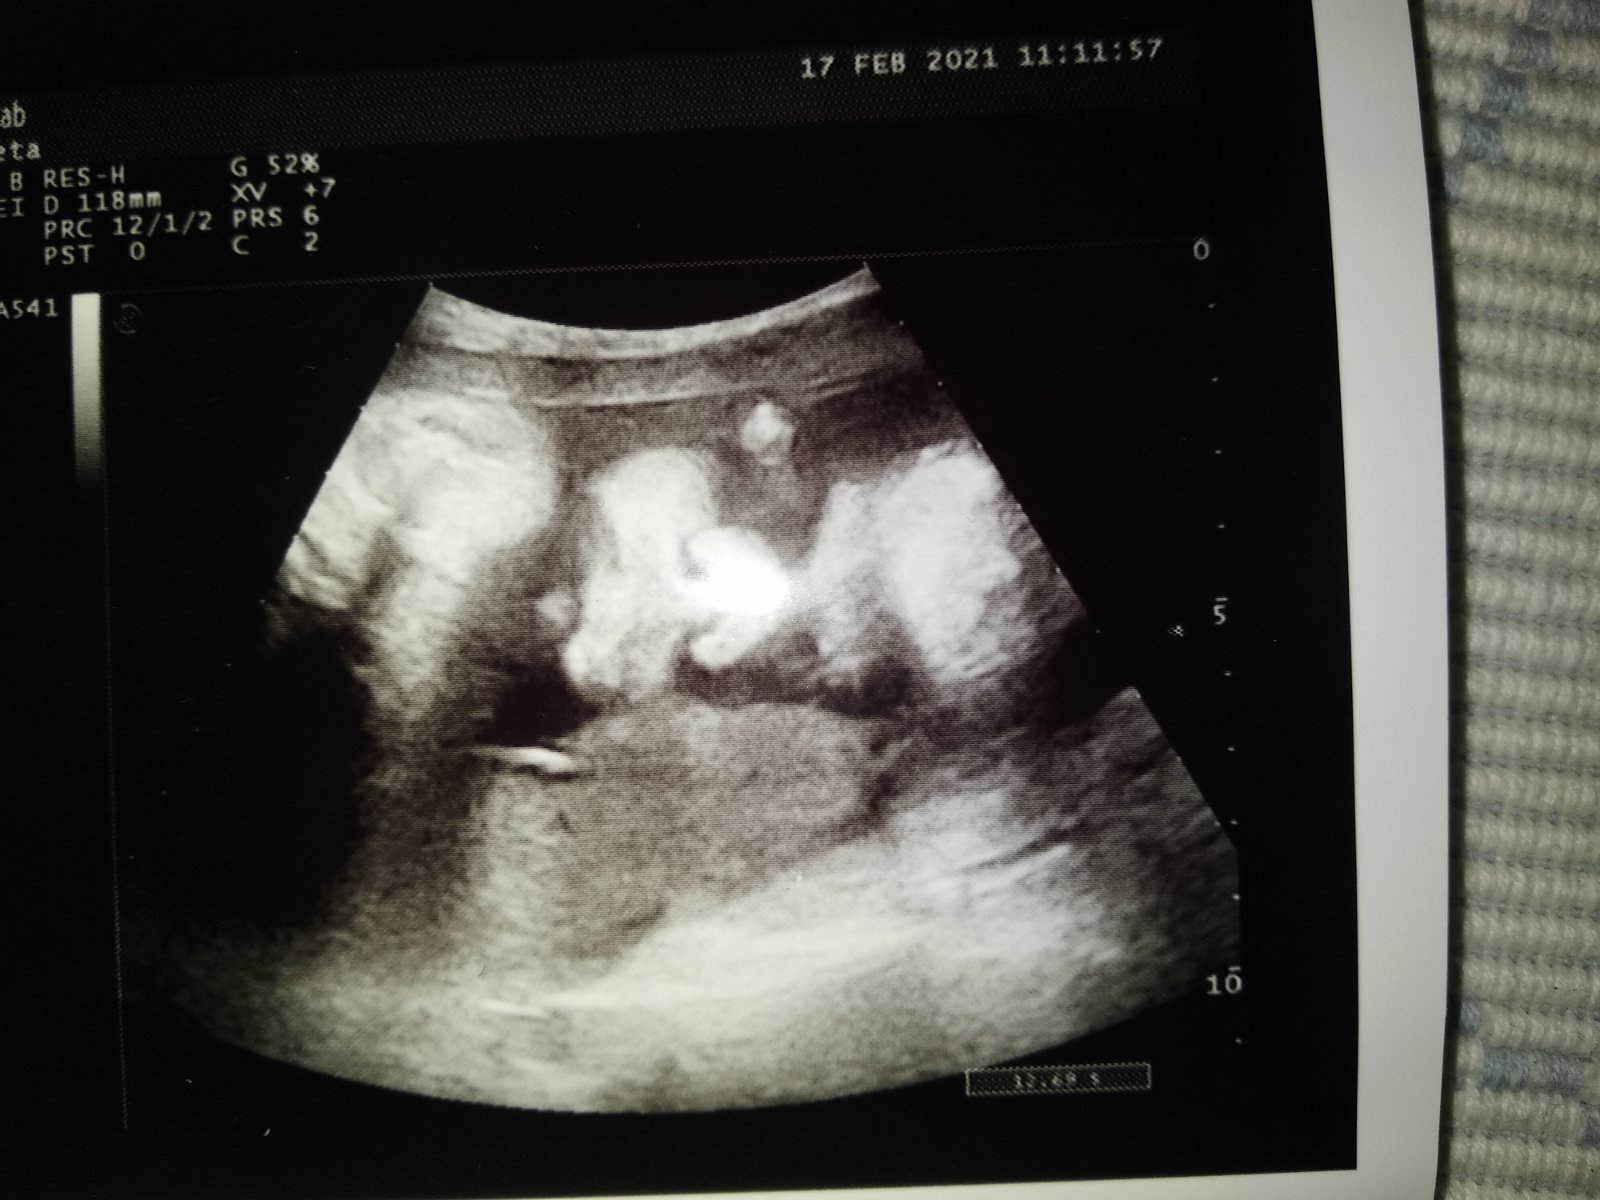

@majka_3 joj ďakujem za opýtanie 😘 v nedeľu 34tt dobre celkom len každý mesiac ma posiela moja na prietoky straší ma a v nemocnici pozeraju ci je moja doktorka v pohode ze mala je tip top v poriadku jedine ma menšie bruško....ale šak je baba ta co😂

@alzbeta162 foto z včerajšej poradni sa smejem lebo nos ma pricapeny o brucho moje ta vyzera ako keby dostala bondzu do nosa🙂